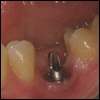

Sofortimplantation Der Begriff Sofortimplantation bedeutet, dass i...